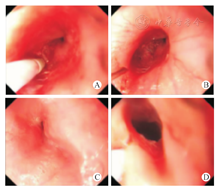

共有5例手术治疗患儿,均为节段性狭窄(图5)。腐蚀性食管狭窄4例,均经食管支架置入治疗效果欠佳,其中男2例,女2例;年龄为(4.00±0.55)岁,狭窄段内径1~4 mm,狭窄段长度50~60 mm;先天性食管狭窄1例(男患儿2岁),狭窄段内径2 mm,狭窄段长度20~30 mm。

狭窄段切除端端吻合术是反复扩张无效的短段型狭窄(狭窄段<2 cm)和确诊气管支气管软骨残留型食管狭窄者的标准术式[20,21]。本研究中5例患儿进行了狭窄段切除端端吻合术治疗,术后恢复良好。食管替代术适用于长段型纤维肌性狭窄、腐蚀性食管狭窄等经扩张无效者,是难治性食管狭窄的常用方法[12]。Takamizawa等[22]和Holler[23]等利用磁压榨吻合成功治疗了食管闭锁和食管狭窄患儿,刘仕琪等[24]、叶明棠等[25]近年亦相继报道该技术在食管吻合方面的成功应用。食管狭窄手术后常见并发症:①吻合口漏,常于术后食管造影时发现,经禁食及抗生素治疗多可愈合,但部分患儿需要置入覆膜支架[15];②吻合口再狭窄,常于食管造影检查时发现,狭窄较重者或有临床表现者可再行食管扩张术;③反流性食管炎,可用药物如抑酸制剂、H2-拮抗药、质子泵抑制药、食管动力药等治疗,如药物不能控制,则需要行胃底折叠术。外科手术治疗的5例患儿,术后未见明显并发症。本中心的治疗经验认为如下条件的患儿须进行外科手术治疗:①反复扩张等治疗无效的难治性食管狭窄;②气管支气管软骨残留型食管狭窄;③长段型纤维肌性狭窄食管狭窄;④长段型食管狭窄(≥5 cm)。